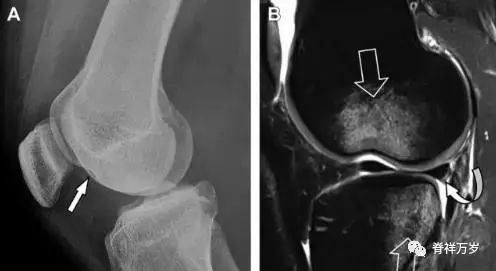

15腓骨头撕脱性骨折

膝关节外侧由髂胫束、股二头肌和肌腱、外侧关节囊韧带及外侧副韧带组成。外侧副韧带对抗过度内旋*力暴**,维持膝关节稳定。当内旋*力暴**足够大时,韧带断裂或腓骨头撕脱性骨折就发生了。在 X 线片上,骨折线垂直于股骨头外侧(图 8)。

图 8 过度伸展引起的腓骨头撕脱性骨折

A 侧位片示腓骨头外侧的垂直骨折(箭头)。B MRI 冠状位 T1 加权像示骨折碎片同时附着于外侧副韧带(箭头)和弓状韧带上(弧形箭头)。